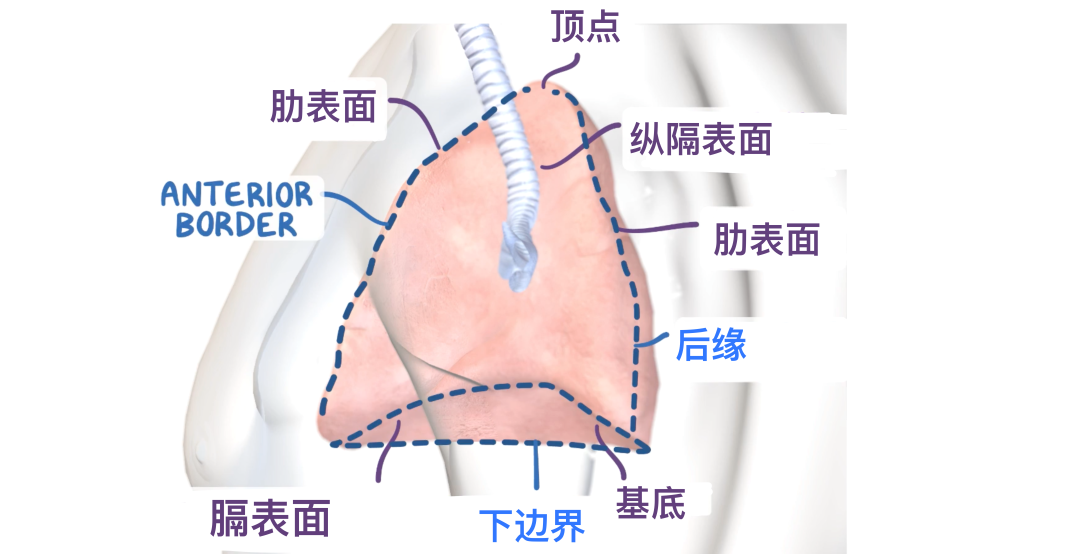

肺部具有轻、柔软、呈现海绵状等特点,每个肺都有一个肺尖和一个基底,3个表面:肋、纵隔和膈,以及3个边界:前、下和后。

顶点是位于颈部根部的第一肋骨水平之上的肺的钝上端,而基部是位于膈肌上的肺的凹下表面。

关于边界,前缘是肋表面和纵隔表面前面相交的地方。在右肺,它几乎是直的,而在左肺,它因心切迹而偏离。下缘薄而尖锐,界定肺的膈表面并将其与肋和纵隔表面分开。它还伸入胸膜的肋膈隐窝。后缘是肋面和纵隔面向后相交的地方,宽而圆形,位于脊柱胸椎区域的侧面。